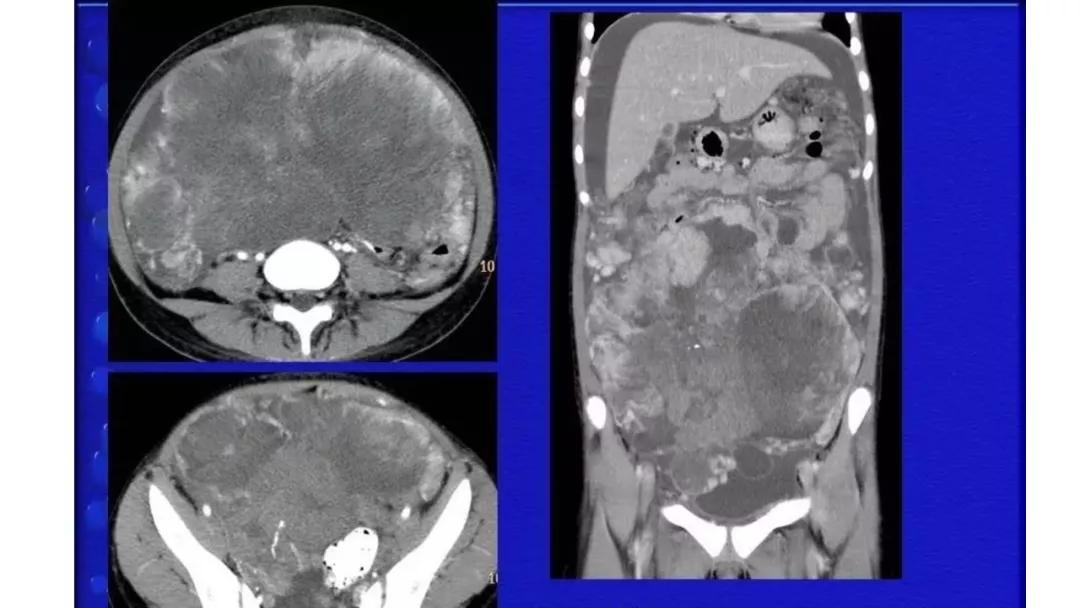

恶性者常呈实性或混杂性肿块,多数边界清楚,可伴有不规则沙粒状钙化。无性细胞瘤常为实性肿块,轻度强化,内胚窦瘤实性成分明显强化,不成熟畸胎瘤呈混杂密度。结合年龄及临床生化检查,有助于诊断。

AFP升高:卵黄囊瘤、无性细胞瘤、混合瘤